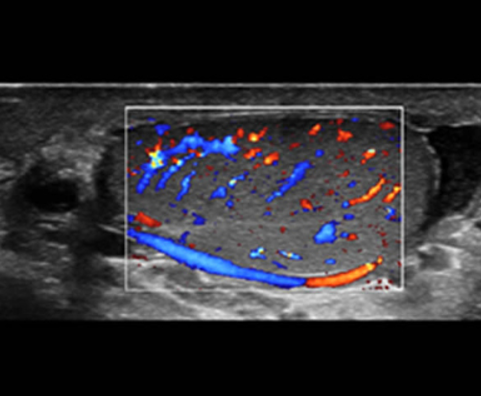

AdemÃĄs de una calidad superior de la imagen, el Resona 7 tambiÃĐn mejora las capacidades de investigaciÃģn clÃnica gracias al revolucionario V Flow para la evaluaciÃģn hemodinÃĄmica vascular y la adquisiciÃģn de planos mÃĄs inteligente a partir de un conjunto de datos 3D para el diagnÃģstico CNS fetal. Combinando el funcionamiento multitÃĄctil mÃĄs intuitivo basado en gestos y todas las funciones clÃnicas esenciales, el Resona 7 estÃĄ realmente encabezando nuevas ondas en la innovaciÃģn del campo del ultrasonido.